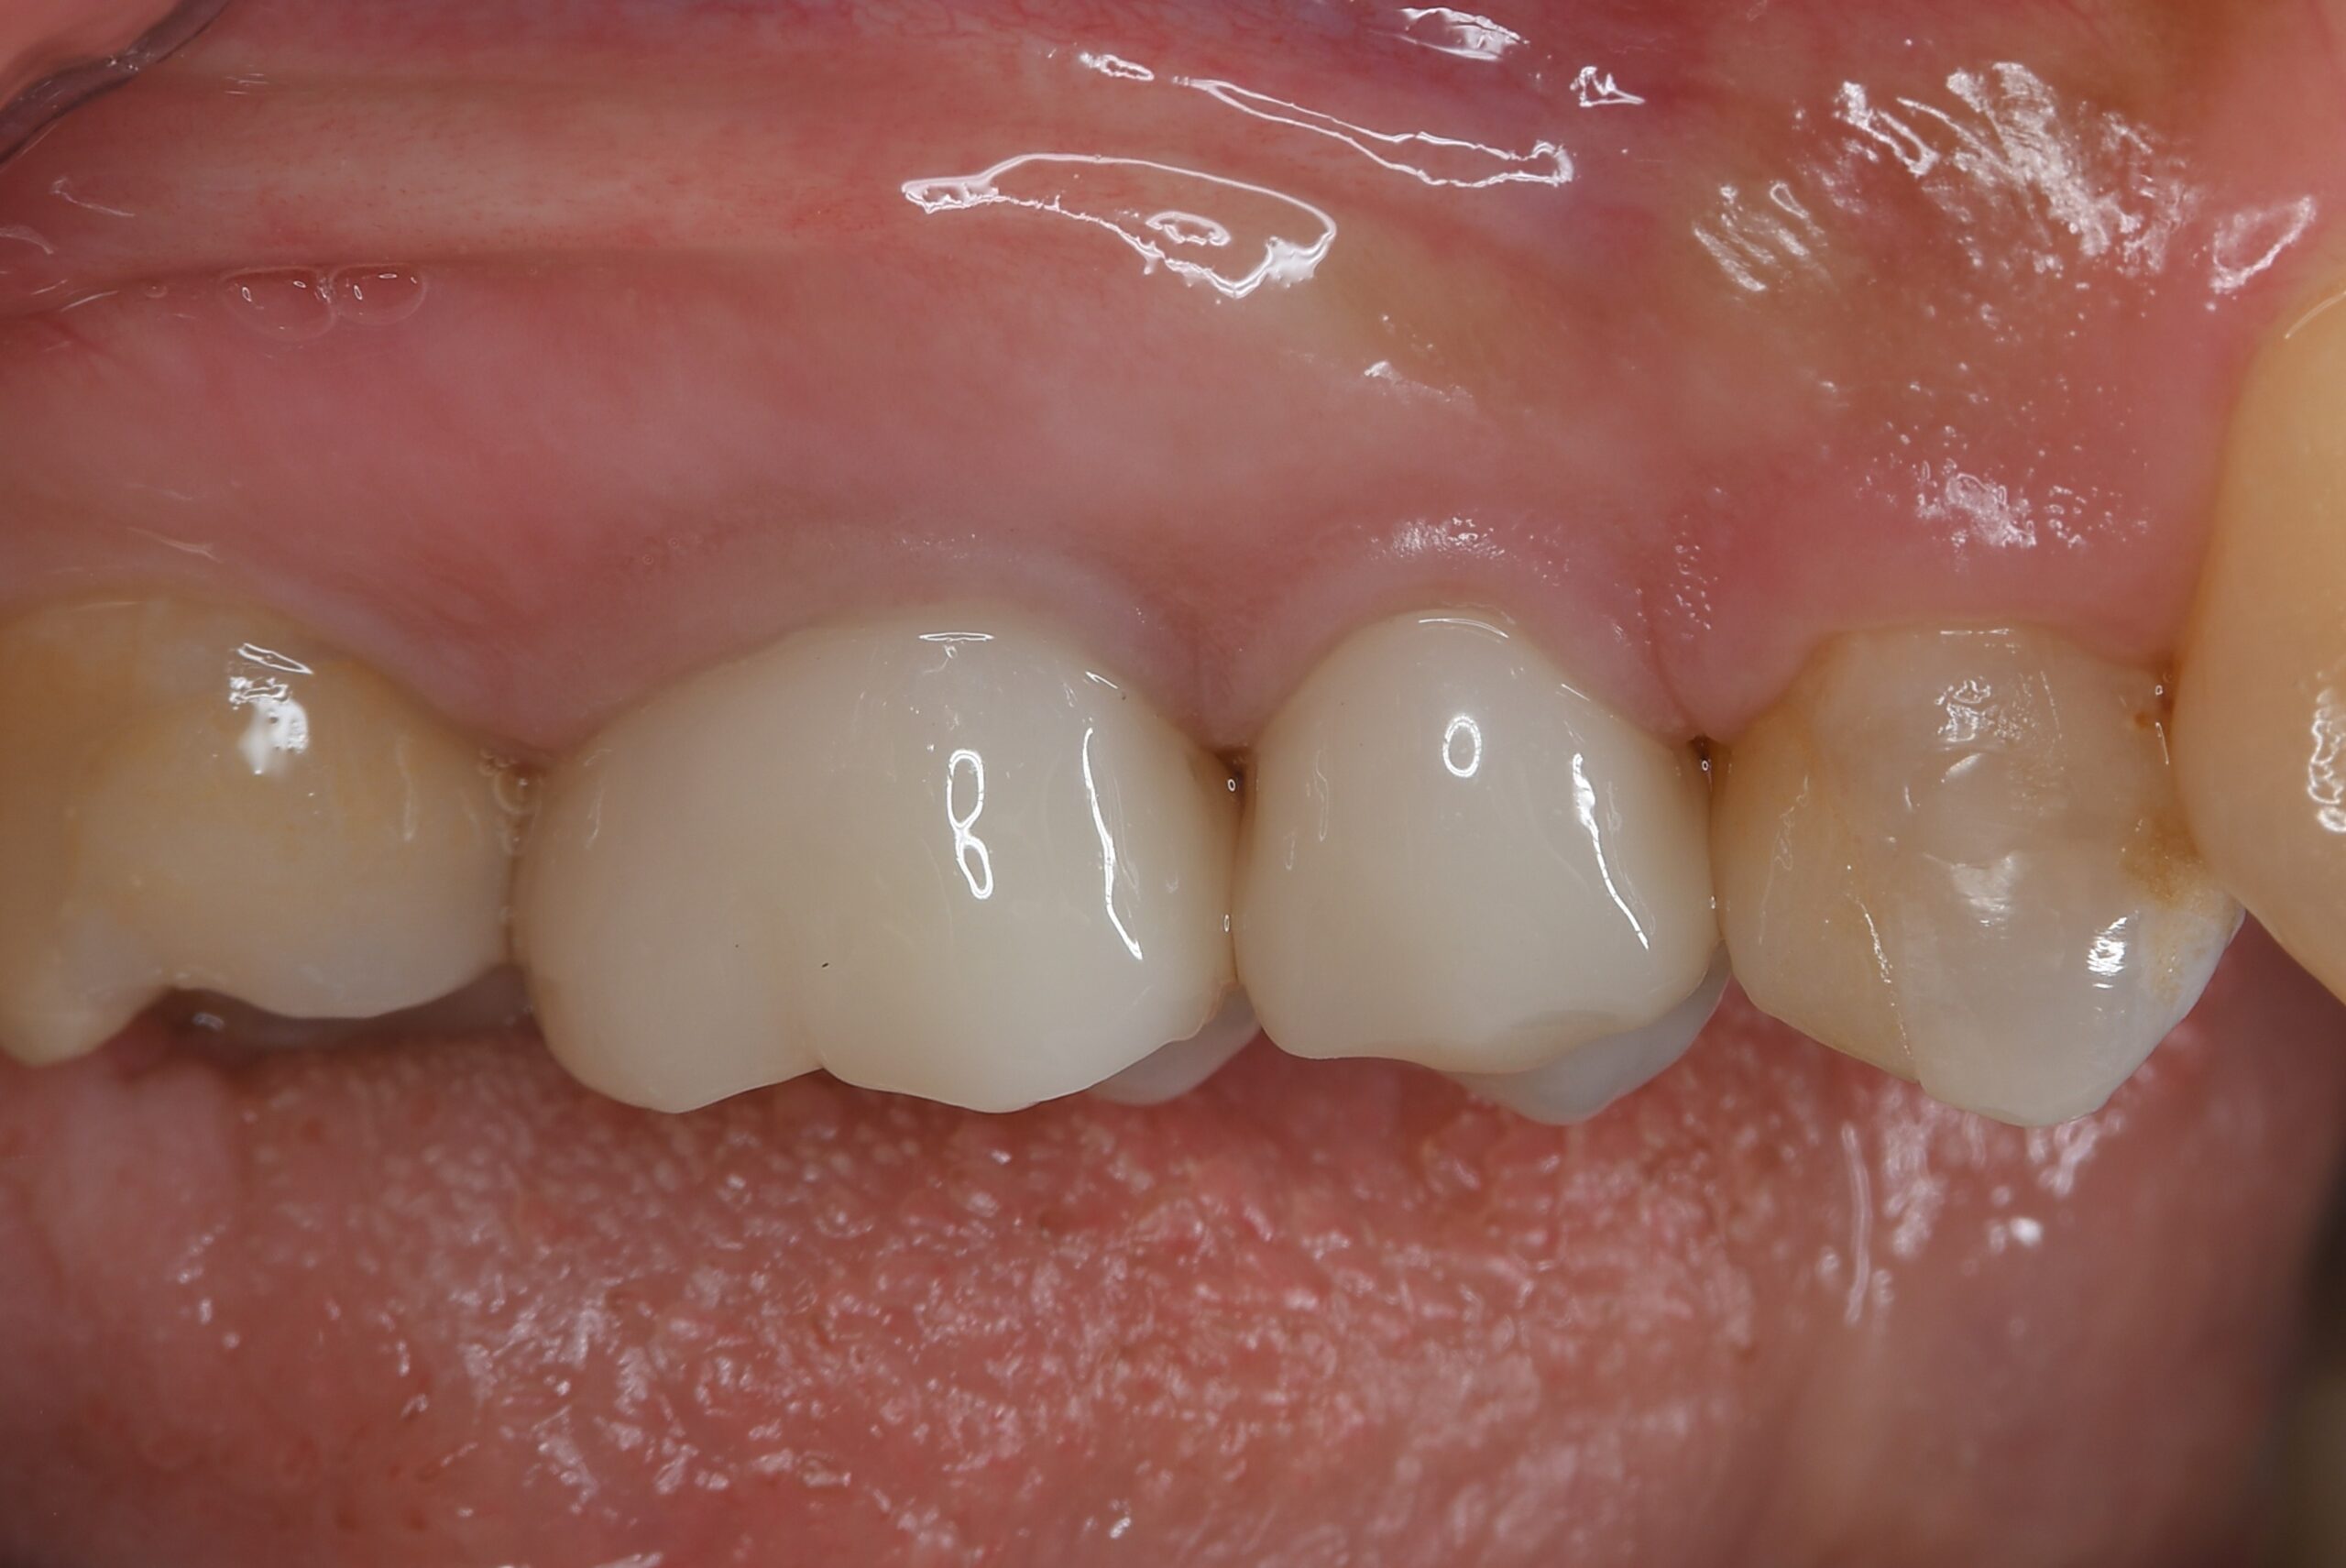

AFTER |

人為的根穿孔を起こした部分に感染を起こしており、歯周ポケットが9㎜ありました。 ラバーダム防湿とマイクロスコープを使用して丁寧に治療を行いました。 殺菌性があり歯を補強することのできるMTAという根管充填材料を使用して、歯周ポケットは2㎜に改善しました。 |